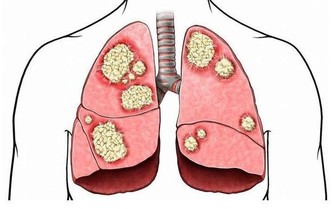

幾乎所有癌症的誘因裡都有它們的身影。有研究認為,吸煙可以對肺、大腸產生長期性、持續性的慢性刺激,從而誘發肺癌、大腸癌。